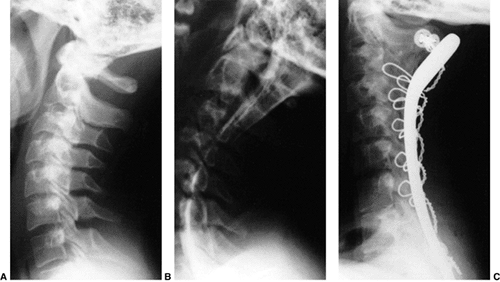

Figure 22.6 A: The posterior cervical line referred to by Swischuk. In C2-C3 pseudosubluxation, the posterior cervical line may pass through (a), touch (b), or lie 1 mm in front of (c) the cortex of the posterior arch of C2. B and C:

Lateral cervical radiographs of a child 2 years and 6 months of age with pseudosubluxation at C2-C3. The radiograph in extension (B) demonstrates no step-off at C2-C3, whereas the radiograph in flexion (C) demonstrates a step-off at C2-C3 (arrow), but with a normal posterior cervical line (solid line). Also note the anterior wedging of the C3 vertebral body, and the overriding of the anterior arch of the atlas on the tip of the odontoid in extension. (A from Shaw M, Burnett H, Wilson A, et al. Pseudosubluxation of C2 on C3 in polytraumatized children—prevalence and significance. Clin Radiol 1999;54:377–380, with permision.) |